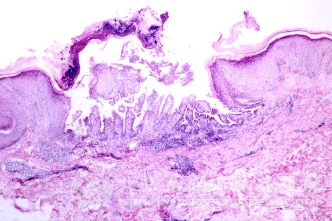

针对外阴毛囊炎的病因有什么,北京京城皮肤医院指出,目前导致外阴毛囊炎病症出现的原因是由于外阴部易沾染尿液、粪便、白带,使外阴皮肤经常处于潮湿的环境中,适于细菌生长。搔抓、摩擦、高温、潮湿、多汗为外阴毛囊炎的诱发因素。